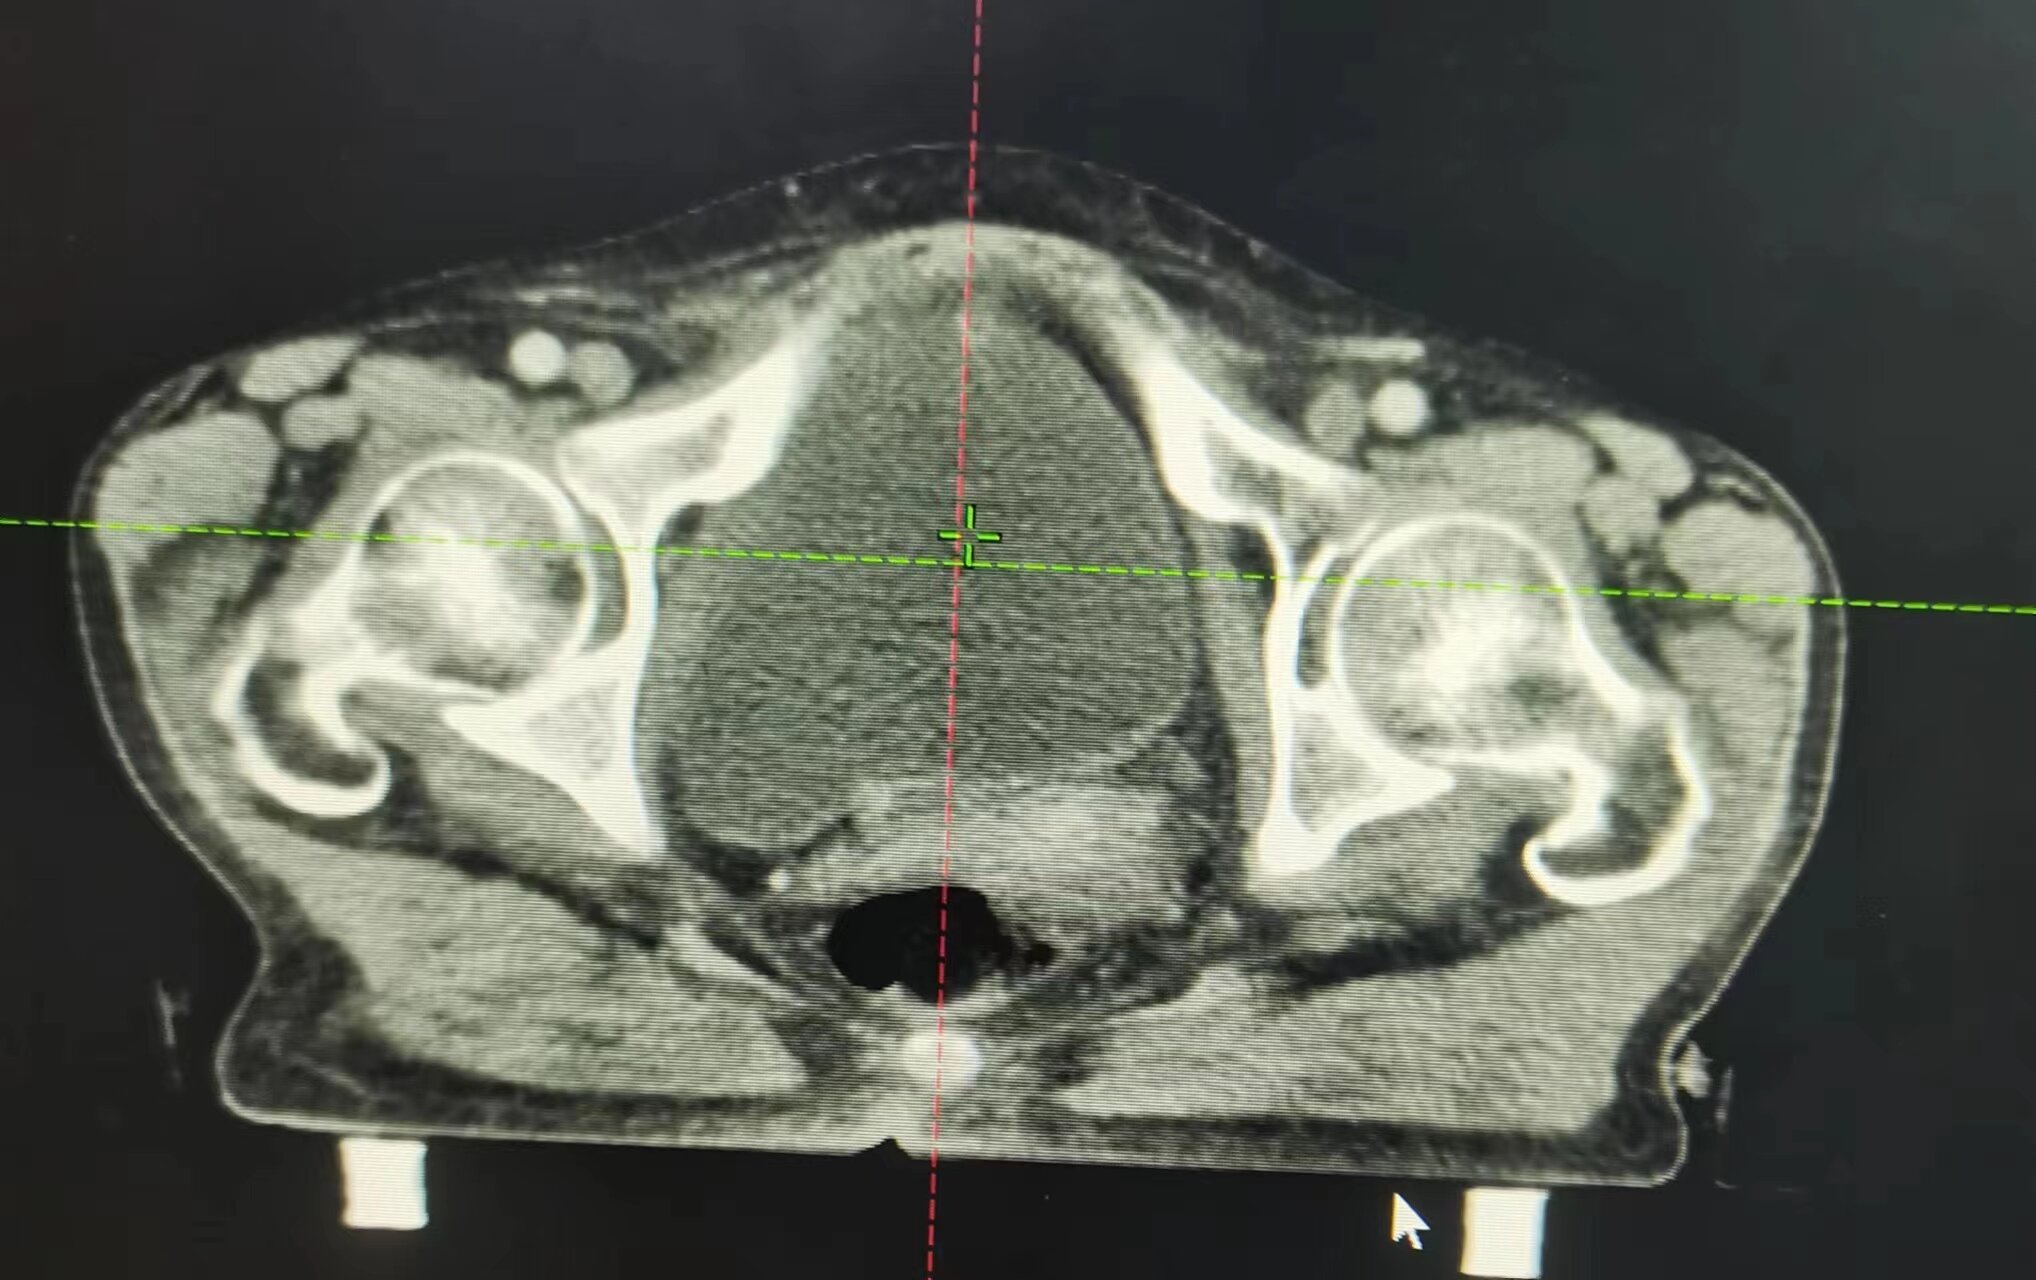

近日,75歲的宮頸癌晚期患者朱阿姨,接受市二院放療科的16次精準(zhǔn)放療后,復(fù)查CT顯示:腹膜后及盆腔轉(zhuǎn)移淋巴結(jié)消失,宮頸腫瘤較前明顯縮小。

朱阿姨被確診宮頸癌后,每天嚴(yán)重的陰道出血及腹部疼痛,使她受盡癌痛的折磨并且心情極度抑郁。3月中旬老人突然腹痛伴陰道大出血,家屬急忙帶朱阿姨來到市二放療科找到趙亮主任,入院后明確診斷為宮頸癌腹膜后及盆腔部位淋巴結(jié)轉(zhuǎn)移。

因老人出血量較大,趙亮接診后立即給予止血治療,出血暫時控制住了,但是腫瘤消不掉,出血現(xiàn)象還是會反復(fù),甚至可能出現(xiàn)危及生命的大出血。考慮到患者病期晚、年齡大、合并基礎(chǔ)疾病多,趙亮帶領(lǐng)科室團(tuán)隊經(jīng)過仔細(xì)討論及評估病情后,決定盡快進(jìn)行三維精準(zhǔn)放射治療及同步化療,同時給予止血及對癥支持治療。